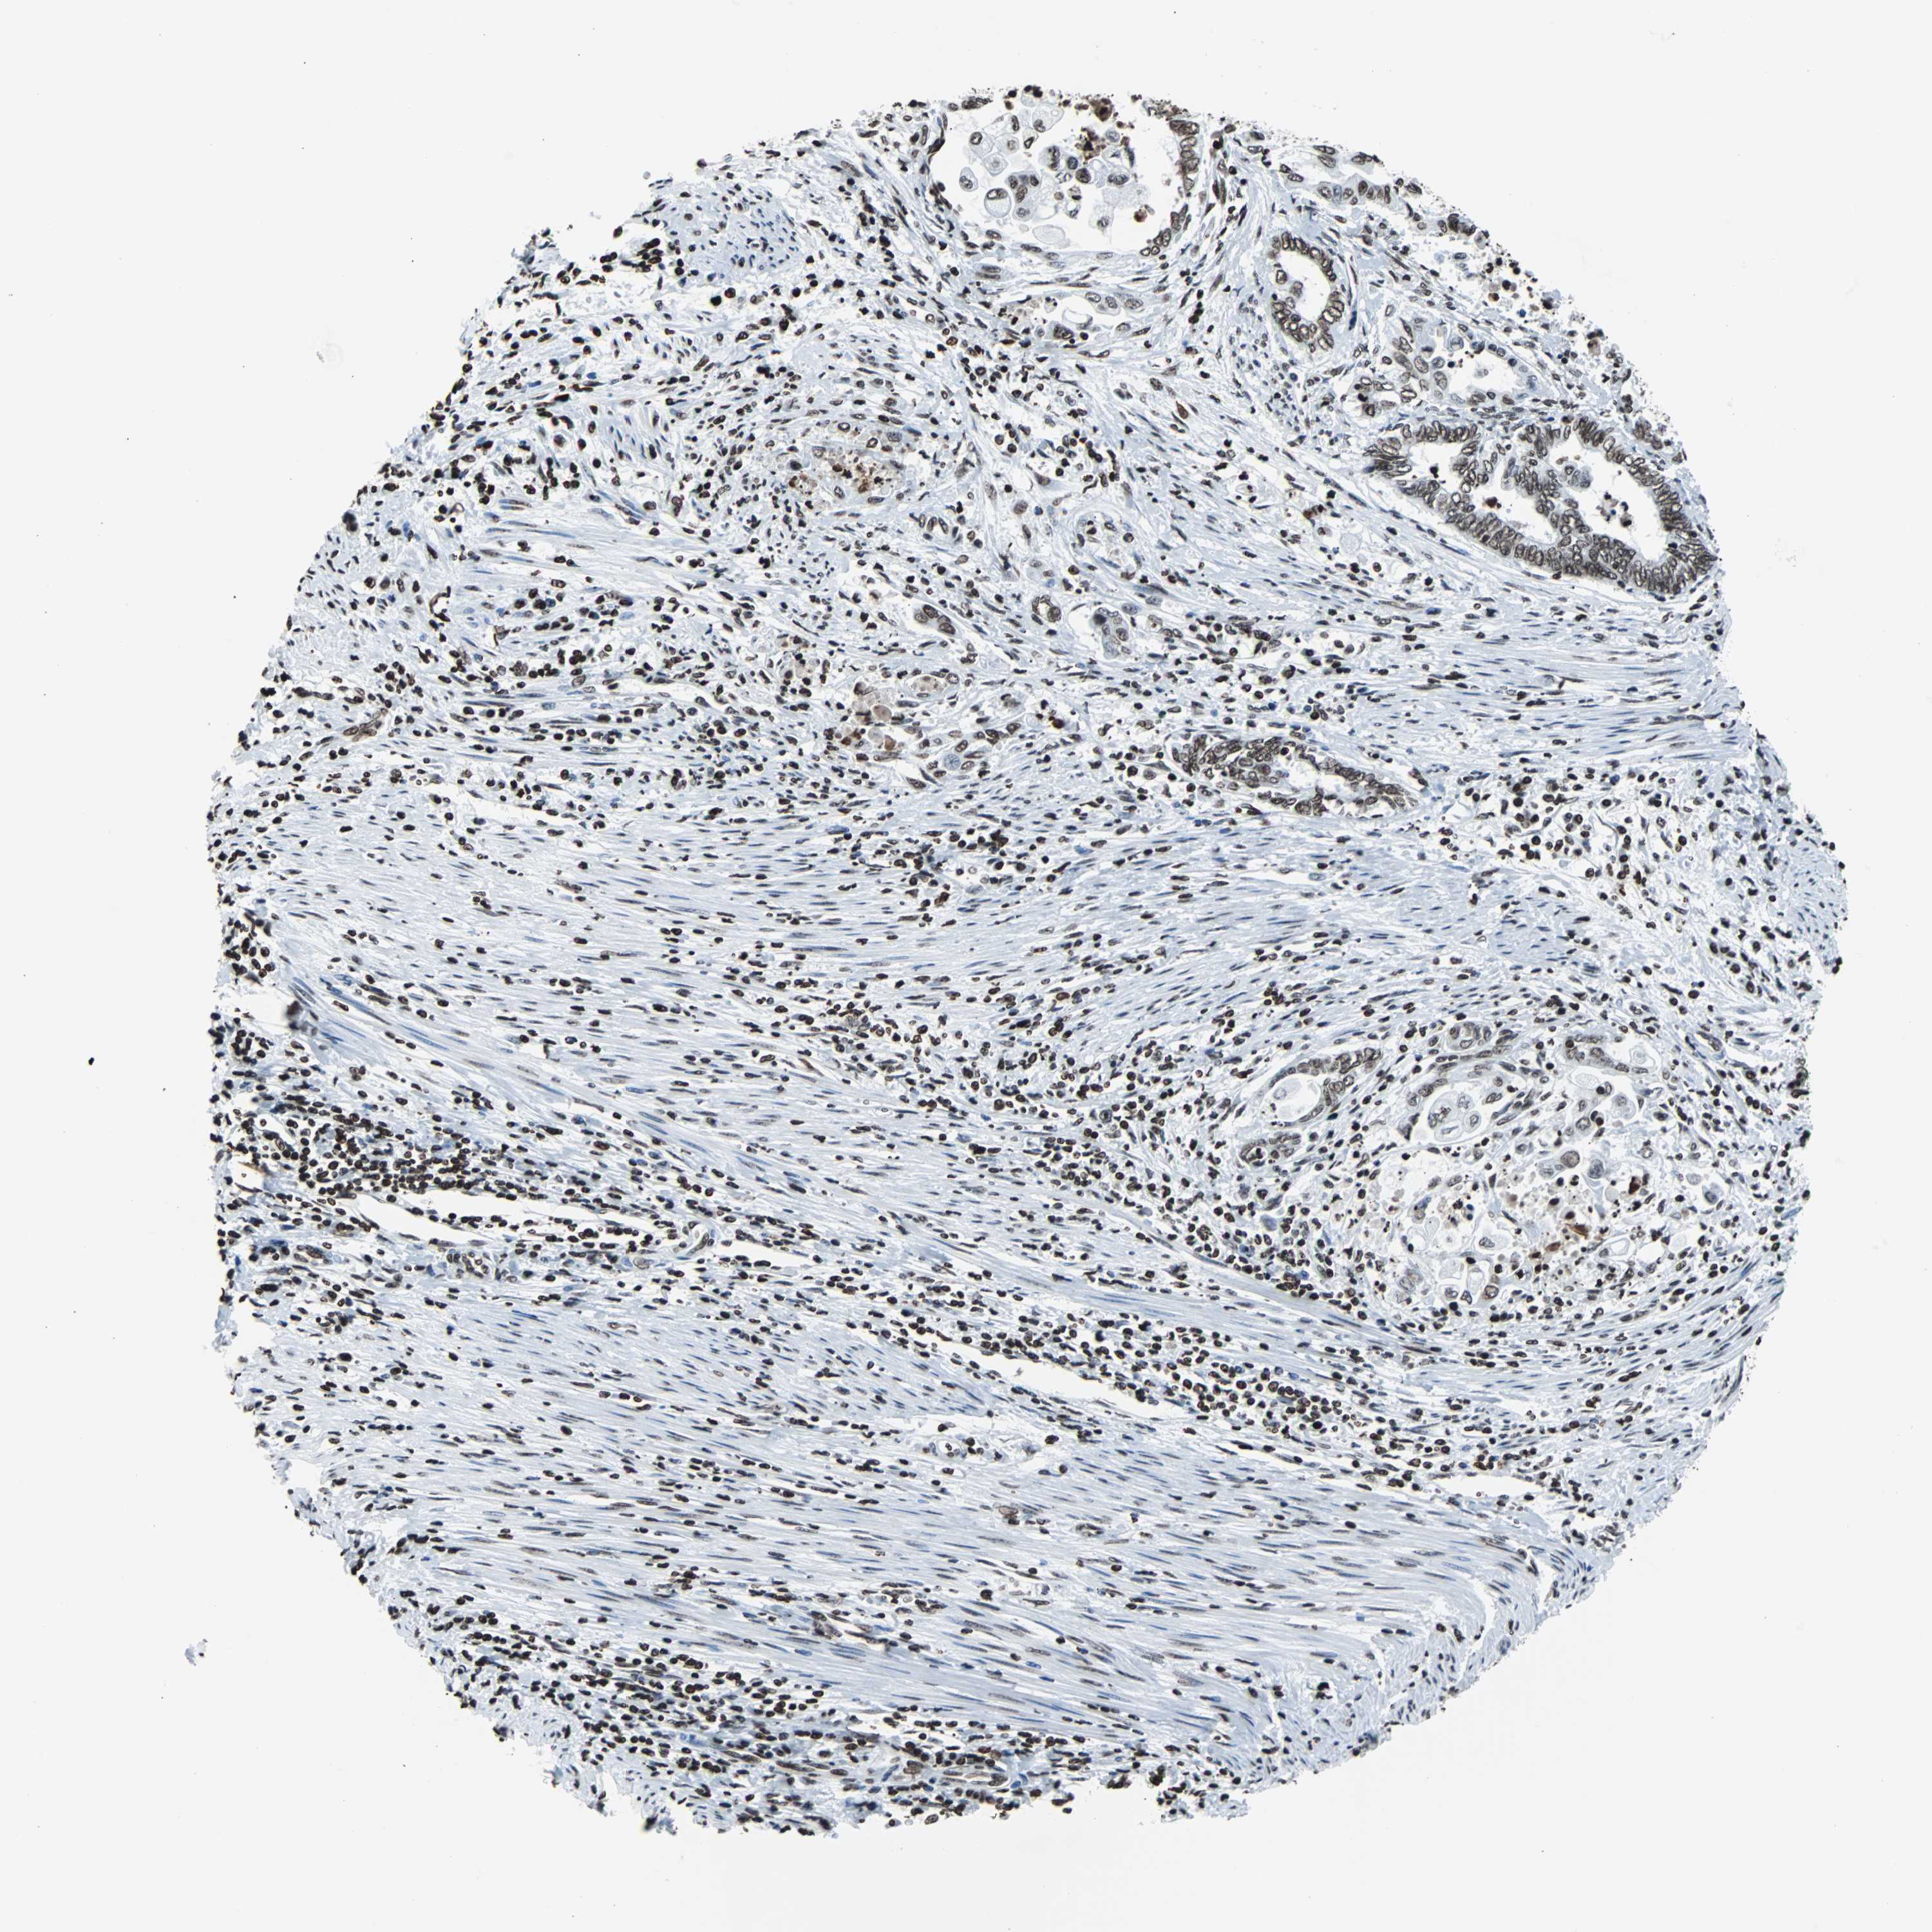

ENDOMETRIAL CANCER - Protein expressioni

A mouse-over function shows sample information and annotation data. Click on an image to view it in a full screen mode. Samples can be filtered based on level of antibody staining by selecting one or several of the following categories: high, medium, low and not detected. The assay and annotation is described here.

Note that samples used for immunohistochemistry by the Human Protein Atlas do not correspond to samples in the TCGA dataset.

Antibody stainingi

Antibody staining in the annotated cell types in the current human tissue is reported as not detected, low, medium, or high, based on conventional immunohistochemistry profiling in selected tissues. This score is based on the combination of the staining intensity and fraction of stained cells.

Each image is clickable and will lead to virtual microscopy that enables deeper exploration of all samples and also displays staining intensity scores, fraction scores and subcellular localization as well as patient and tissue information for each sample.

Antibody HPA042205

Antibody HPA043013

Antibody HPA048671

Antibody CAB007814

Staining

High

Medium

Low

Not detected

Intensity

Strong

Moderate

Weak

Negative

Quantity

>75%

75%-25%

<25%

None

Location

Nuclear

Cytoplasmic/membranous

Cytoplasmic/membranous,nuclear

Adenocarcinoma, NOS